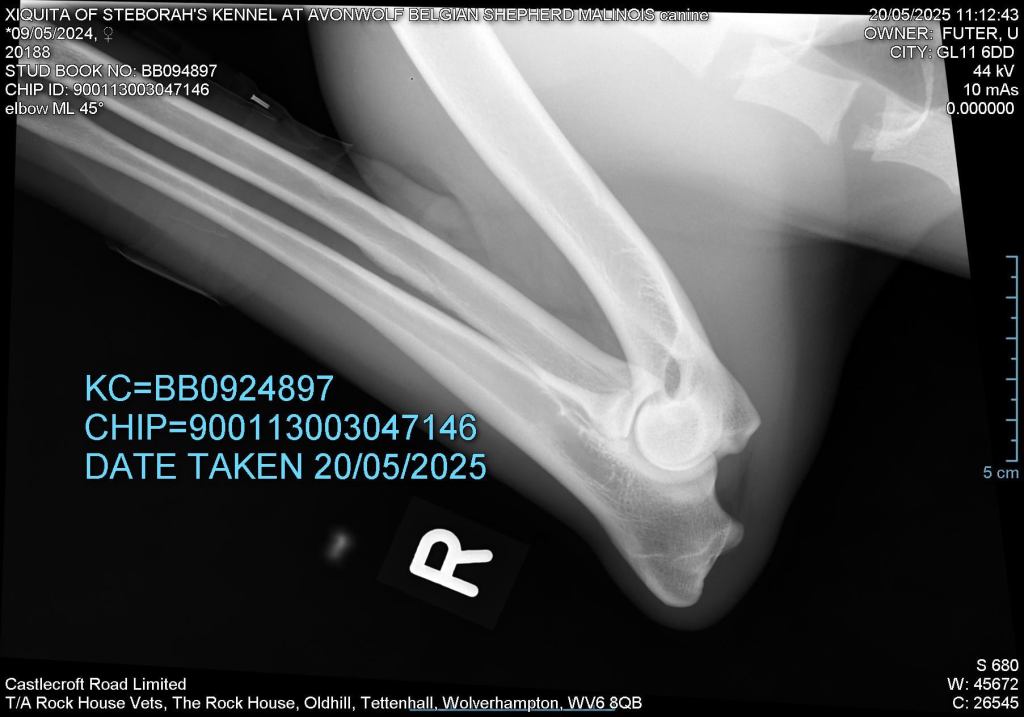

Elbows 0/0